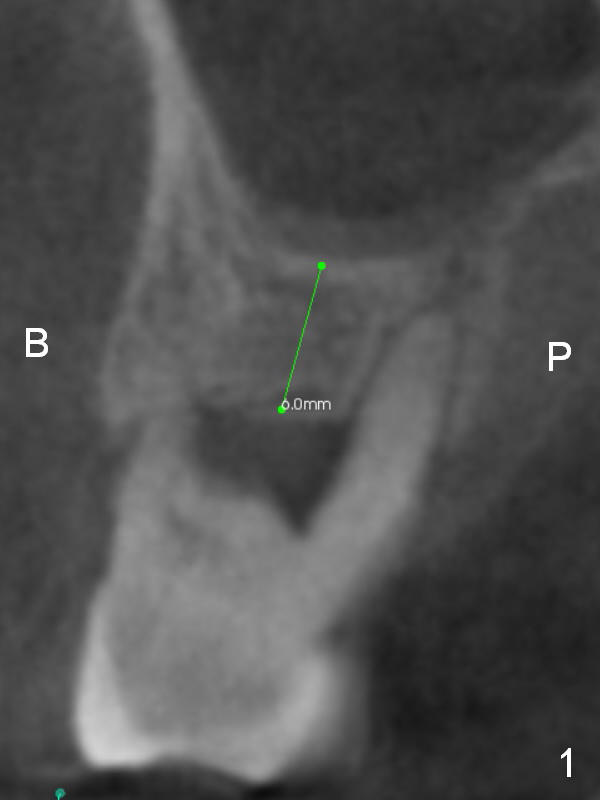

A 44-year-old man requests an implant at #3 because of mobility. It appears that the bone height decreases from 6 mm (Fig.1,2: 3 years ago) to 4 mm (Fig.3,4, recently). After extraction and Clindamycin treatment, take PVS impression of the socket. Use initial drill with drill stopper of 3 mm and round burs with stoppers from 4 to 5 mm. If the buccal (B) and palatal (P) plate defect is severe, use a regular implant. Otherwise use an extra wide one. The advantage of the latter is length as short as 6 mm vs. 8 mm for the regular one. For the latter, 2 mm of the implant will be in the sinus (Fig.4 red box), 4 mm in bone (pink box) and 2 mm in the socket (orange box; to be surrounded by bone graft). Since the gingiva is 6 mm (Fig.4 green box), an abutment with 6 mm cuff should be chosen. To reduce occlusal interference, select abutment height 4 mm.